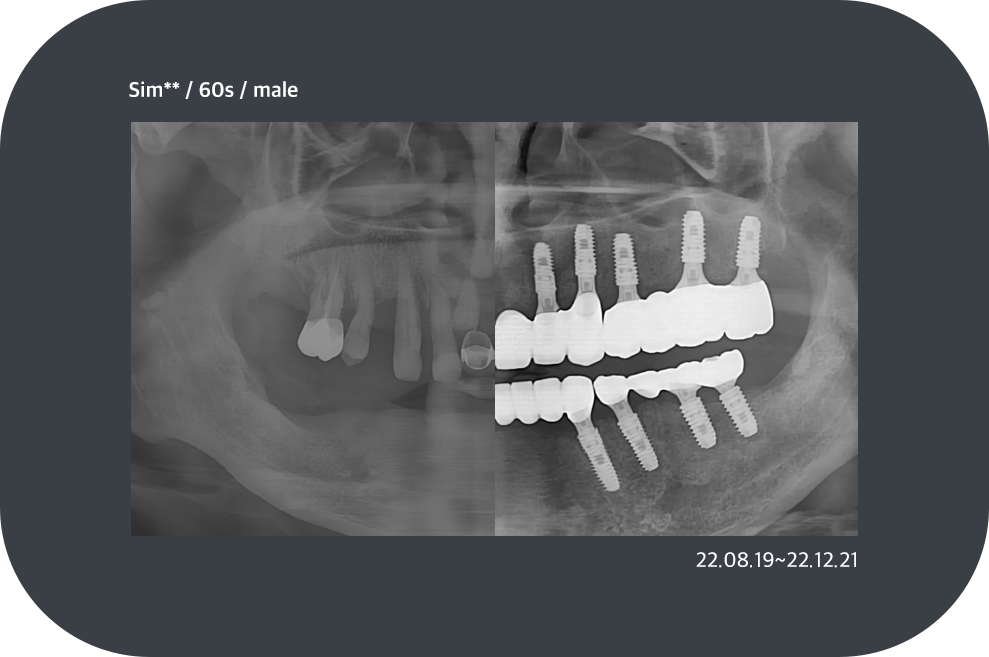

치료사례

임플란트 치료사례

*모든 증례 사진은 의료법 제23조, 제56조에 의거하여, 당사자의 동의하에 게시하였습니다.

*치료 사진은 모두 본원에서 치료한 환자분의 사진입니다.

*치료 사진은 모두 동일인의 사진이며, 동일조건에서 촬영하였습니다.

*개인의 차이에 따라 시술 및 수술 후 부작용이 발생할 수 있으며, 의료진과 충분한 상담을 받으시기 바랍니다.